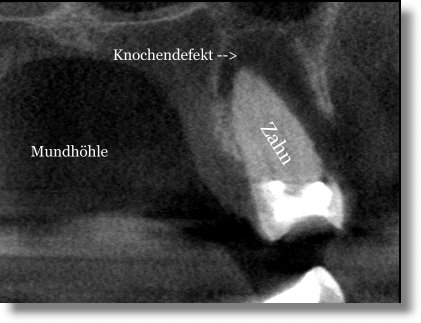

Schnittbild der betroffenen Region

In der Einzelanalyse der Schnittbilder erkennt man deutlich das imense Ausmaß des Knochenabbaus (dunkler Bereich). Der Zahn hat entzündungsbedingt kaum noch Kontakt zu gesundem Knochengewebe und konnte nur mit großem Aufwand noch gerettet werden.